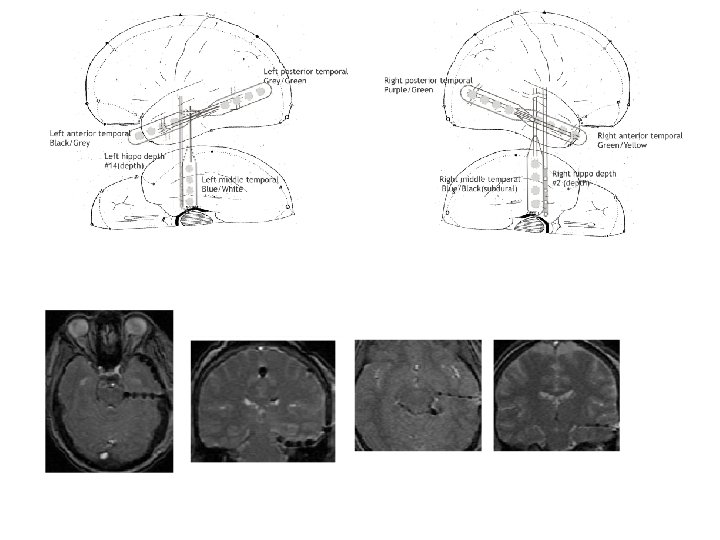

An individual patient may have more than one morphology and/or localization of seizure onset Next seizures all from same patient, now seizure free >1 year after right anterior temporal lobe resection

Five different seizure onsets recorded from intracranial depth electrodes in one patient over 24 hours